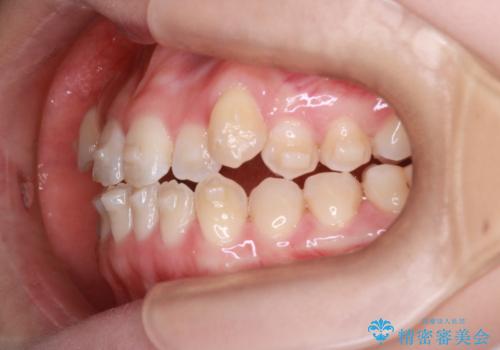

MARPEで非抜歯矯正|オープンバイトと八重歯を改善

- 治療計画

上顎にTAD(矯正用アンカースクリュー)を設置し、MARPEにより骨格レベルで上顎の幅を拡大。数週間の拡大期間を経て十分なスペースを確保したのち、マウスピース型矯正装置(インビザライン)で歯列全体を整えました。八重歯もアーチ内に自然に収まり、非抜歯で審美性と機能性を両立。治療後は「噛み合わせが安定して笑顔に自信が持てるようになった」とご本人にも大変満足していただきました。